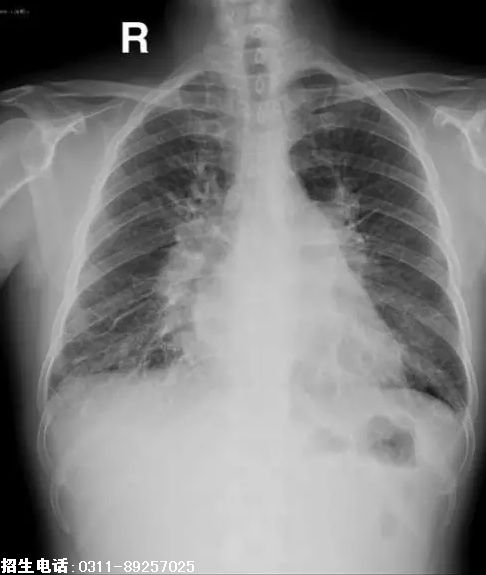

1、题干:男,55岁。腹痛,呕血1次。结合X线片,此诊断为

答案:B

解析:心脏投影呈现梨形,主要是心腰部分向外膨大的一种体现如下图。由于心脏的心腰部份是肺动脉和左心房共同构成。所以任何引起肺动脉膨大(见于肺动脉高压)和左心房扩大(见于二尖瓣狭窄)的疾病都会出现梨形心。尤其是二尖瓣狭窄时更为典型,因为二尖瓣狭窄时除左心房淤血增大外,长时间的肺部淤血还会出现肺动脉高压。这样左房增大和肺动脉高压同时出现使得心腰向外膨出。另外二尖瓣狭窄,流入左心室的血液减少,左心室会较正常减小就使心腰部分的膨大显得更加明显。所以梨形心最常见于二尖瓣狭窄所以又叫作二尖瓣形心。